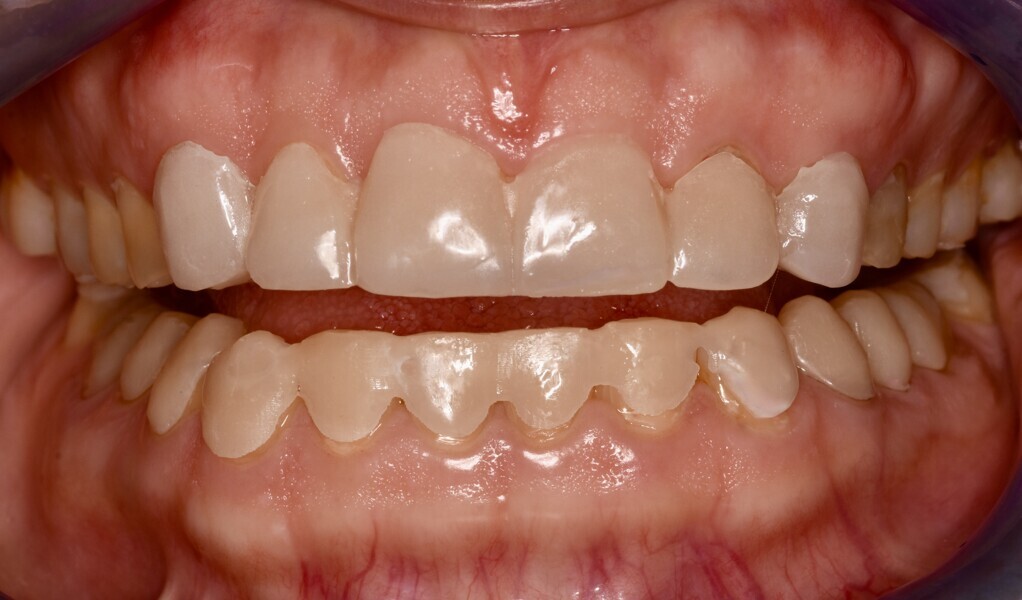

Fig. 1a: Initial situation. Recognisable loss of vertical dimension in the frontal view.